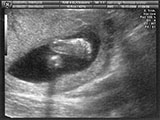

8/3/09. First ultrasound. 8 weeks, 1 day gestation. Looks like we're gonna have a lizard. |

8/3/09. Bottom graph shows heartbeat (already). |